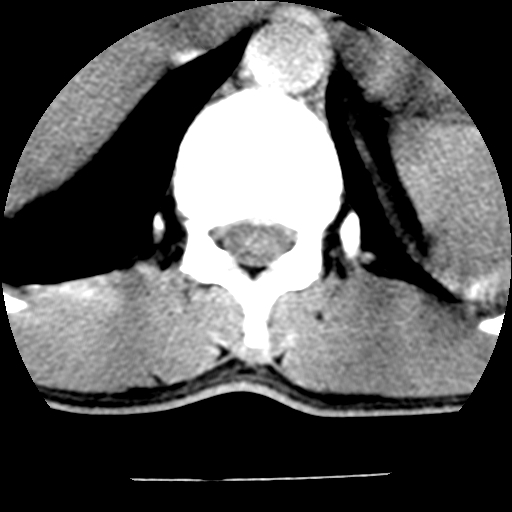

男,31岁,从6米高处坠落伤两天,腰背部疼痛,临床要求ct扫描胸10-腰1。请大家帮忙看看骨质有问题吗?

t12、l1锥体前缘轻度楔形变,平扫示椎体前缘骨小梁欠规整,第9幅图示椎体前缘骨质不连续,结合外伤史考虑椎体轻度压缩骨折。

楼主扫描层厚可能较大,每个椎体只有三个层面.

从所示层面分析,无明确骨折征象,象类似病人我个人会建议mri除外骨挫伤.

从上查骨窗第九片椎体前缘皮质显示断裂.压缩骨折?